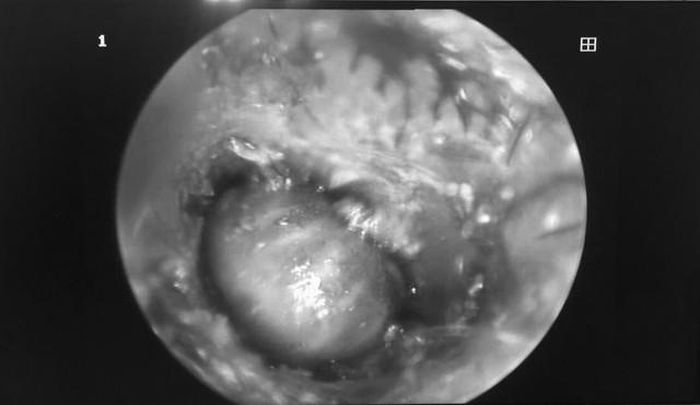

Trẻ 2 tuổi bống nhiên đau nhức tai, chảy dịch gia đình cho đến BV Việt Nam Thụy Điển Uông Bí kiểm tra, kết quả bác sĩ phát hiện ve chó đang sống 'ngoe nguẩy' trong lỗ tai trẻ.

Qua thăm khám và nội soi tai mũi họng, các bác sĩ đã nhanh chóng phát hiện ở vị trí. Theo

BSCKI. Phạm Thị Hồng Vân – Khoa Tai mũi họng bệnh viện cho biết, sau khi gia đình đưa trẻ đến các bác sĩ thự hiện nội soi thì phát hiện ở vị trí rìa màng nhĩ (tai phải) của bệnh nhi có hình ảnh dị vật màu xám đen và có máu cục. Làm sạch máu cục thì phát hiện dị vật là một loại ký sinh trùng - ve chó. Ngay lập tức trẻ đã được lấy bỏ dị vật ra ngoài

Hình ảnh ve chó trong tai bé 2 tuổi (ảnh BVCC)